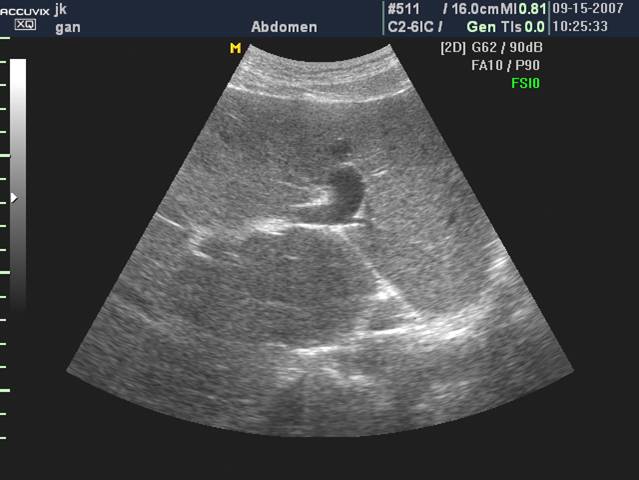

脐静脉重新开放

门静脉海绵样变性

脐静脉重新开放: